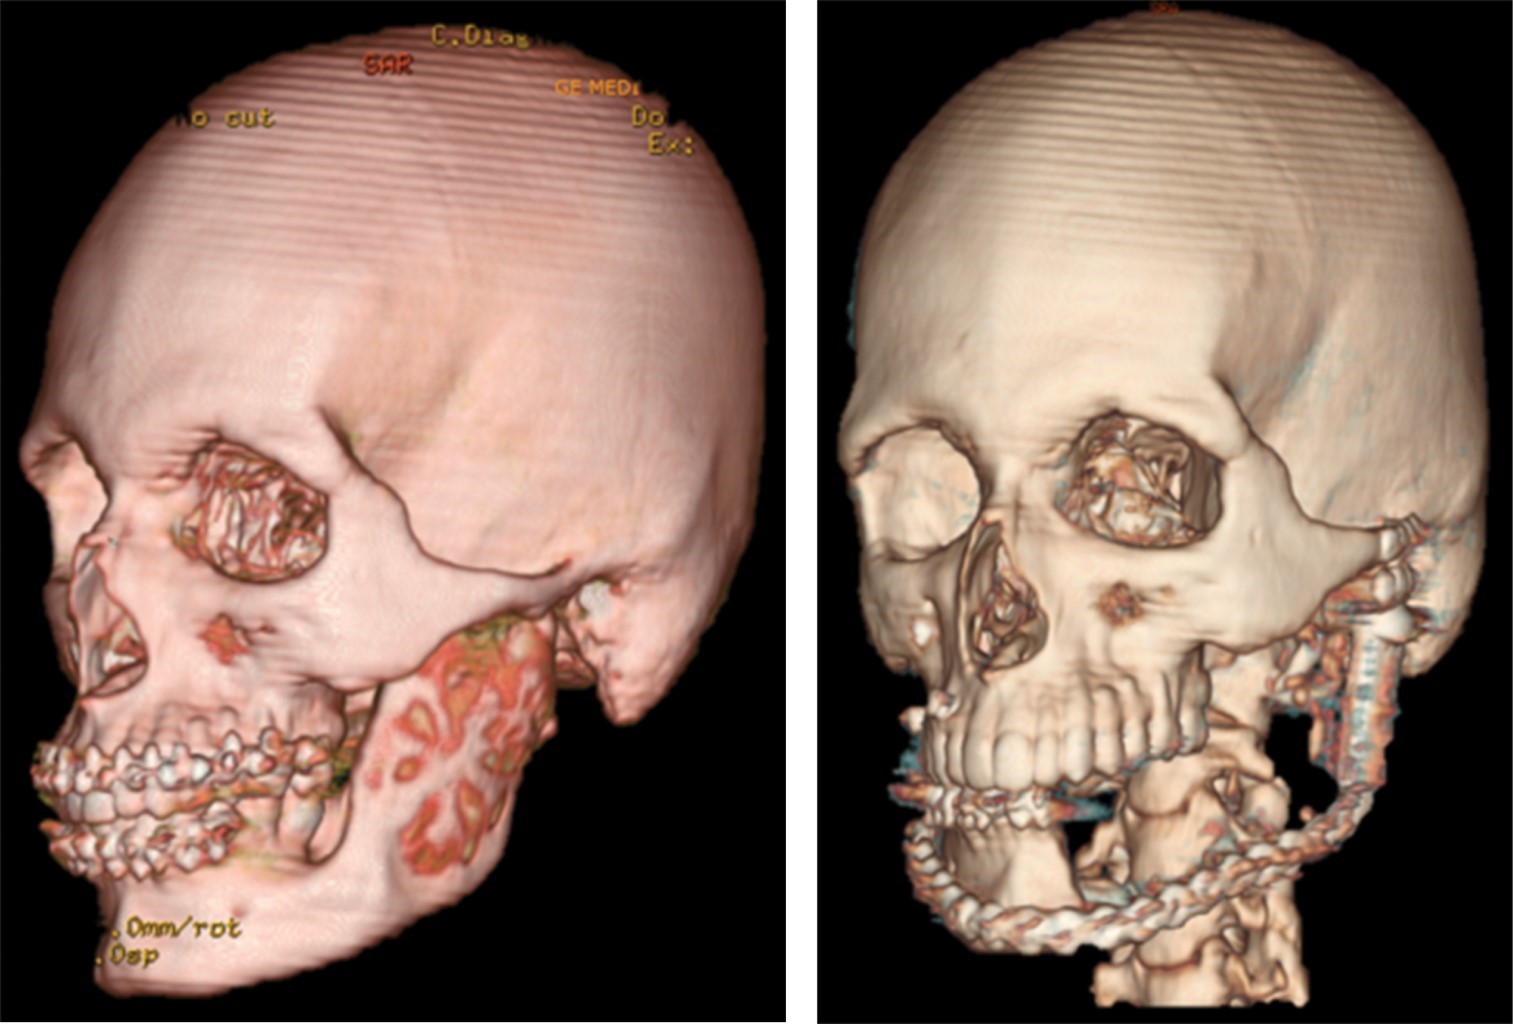

Paciente masculino de 19 años de edad, sin antecedentes patológicos relevantes. Natural y procedente de Yaracal Edo. Falcon, Venezuela. Inicio de enfermedad en junio de 2017. Presenta aumento de volumen progresivo en cuerpo mandibular izquierdo, con resultado de estudio histopatológico previo (2018) de ameloblastoma plexiforme mandibular, motivo por el cual acudió a nuestro servicio para valoración y conducta donde se decidió preparar para acto operatorio en octubre de 2022 (Figuras 1 y 2).

La cirugía fue planificada digitalmente utilizando modelos estereolitográficos con los cuales comprobamos la adaptación de la prótesis customizada, medidas, resección mandibular, cantidad y posicionamiento del material de osteosíntesis (Figura 3). Bajo anestesia general, con intubación nasotraqueal, se realizó hemimandibulectomía total con márgenes de seguridad, desde el cuerpo mandibular a nivel de unidad dentaria 33 hasta el proceso coronoides y el cóndilo mandibular, mediante abordajes preauricular, Risdon y vestíbulo mandibular con extensión a cóndilo izquierdo (Figura 4).

Figura 1

Figura 2